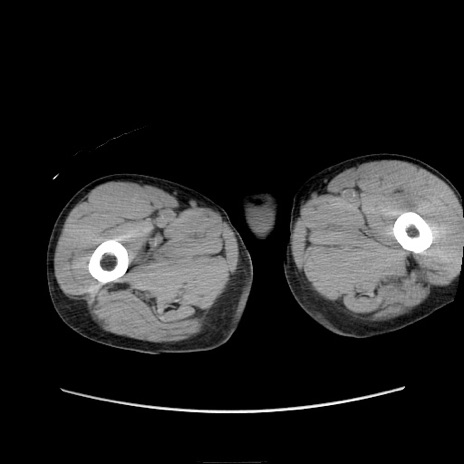

症例11(横断像)

【症例】 60歳代男性

【主訴】 下腹部痛

【現病歴】 本日夜中より下腹部痛の症状認め、受診。

【既往歴】 膀胱癌(膀胱全摘+尿管皮膚瘻術) 、胃癌術後

【身体所見】 BT 35.3℃、PR 58/min、BP 136/98mHg、腹部平坦、軟、腸蠕動音±、ストマ留置あり、左上腹部~正中部に圧痛あり、反跳痛なし。

【データ】WBC 5100、CRP0.01